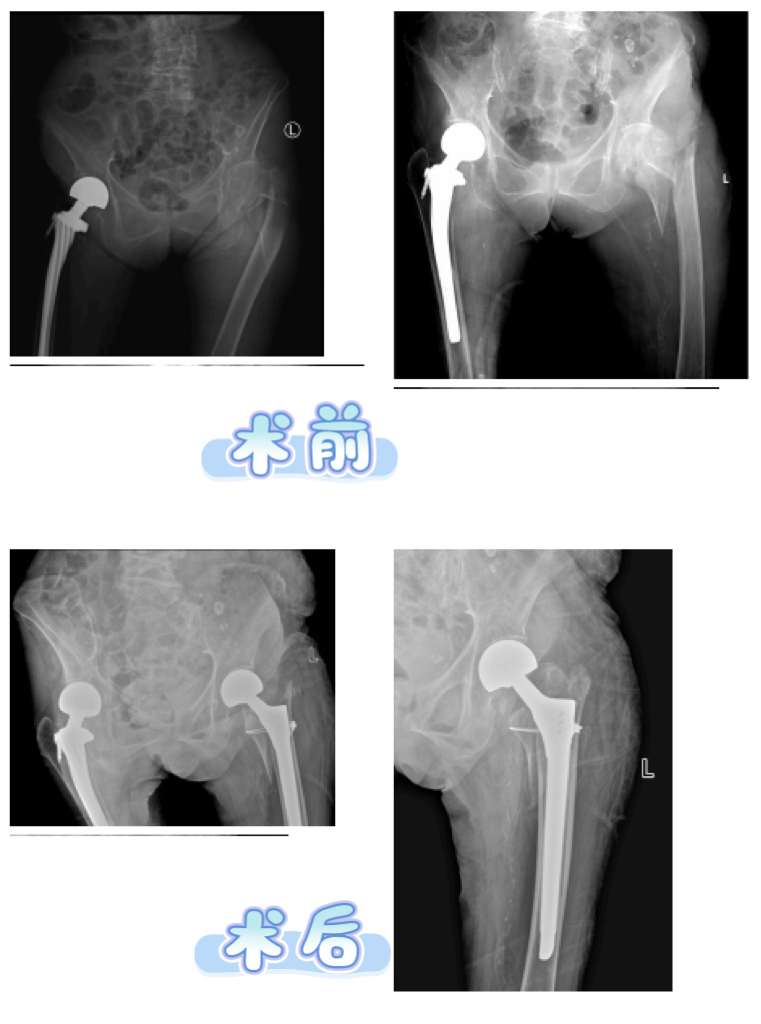

骨质疏松症是一种以骨量减少、骨微结构破坏为特征的全身性骨病,其早期往往无明显症状,但其导致的骨折,尤其是髋部骨折,致残率和致死率极高,给社会带来沉重负担。我国人口老龄化日益严峻,骨质疏松症已经成为不容忽视的公共健康问题。老年人群因身机体功能衰退、平衡能力下…